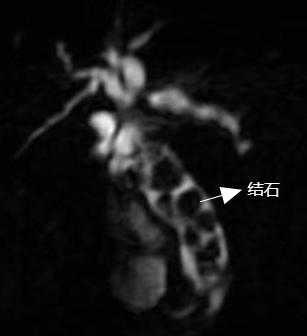

患者女性,97岁,因右上腹疼痛不适1周入院,MRCP检查提示胆总管充满结石,向上累及左右肝管。患者入院时胆红素身高,并胆管炎,有进一步引起梗阻性化脓性胆管炎可能,危及生命,手术治疗势在必行。